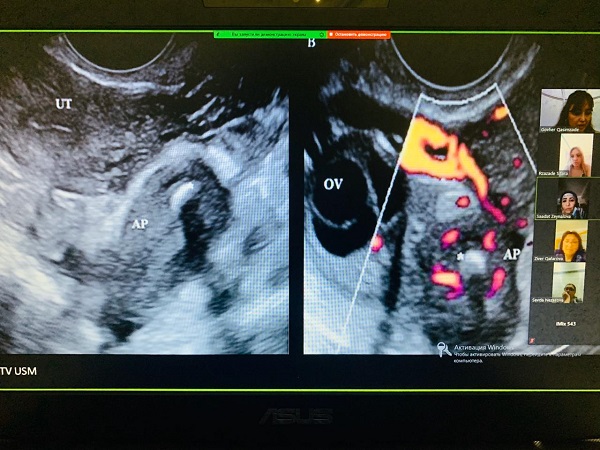

Təhsil proqramlarının mənimsənməsi müxtəlif yeni texnologiyalar vasitələrinin geniş istifadəsi ilə həyata keçirilir. Distant təhsil də davamlı tibbi təhsilin bir növüdür. Son illərdə institutumuzun kafedralarında distant təhsilə xüsusi diqqət yetirilir. DTT-nin tətbiqi ilə əlaqədar təkmilləşdirmə kurslarına olan təlabat artmış və bu xüsusən bölgələrdə çalışan həkimlər üçün məsafədən təhsili günün aktual məsələsi etmişdir. Bunları nəzərə alaraq institutun illik təqvim planında çoxsaylı səyyar/distant kurslar planlaşdırılmış və müvəffəqiyyətlə həyata keçirilmişdir. Beləki, çox saylı həkim kontingenti olan 6 ixtisas (terapiya, pediatriya, şüa diaqnostikası, mamalıq və ginekologiya, stomatologiya, anesteziologiya və reanimatologiya) üzrə Respublika ərazisi 10 zonaya bölünməklə səyyar/distant kurslar elə planlaşdırılmışdır ki, artıq bölgələrdən bu ixtisaslı həkimlərin Bakıya, instituta gəlmələrinə ehtiyac qalmamışdır. Həmin ixtisaslar üzrə institutun nəzdində Bakı, Sumqayıt şəhərlərində və Abşeron rayonunda çalışan eyni ixtisaslı həkimlər üçün təşkil olunan təkmilləşmə kursları paralel olaraq bütün Respublika ərazisinə onlayn translyasiya etdirilmişdir. Təkcə 2019/2020-ci tədris ilində qeyd olunan ixtisaslar üzrə 7000-ə yaxın bölgə həkimi bu tip distant kurslardan yararlanmışdır.

COVID 19 pandemiyası ilə əlaqədar hal-hazırki karantin dövründə tədris prosesində boşluq əmələ gəlməməsi üçün ixtisasartırma kurslarının onlayn tədrisi daha da təkmilləşdirilmiş, genişləndirilmiş və bütün kafedraları əhatə etmişdir. Dərslərin aparılmasında Zoom telekonfrans tətbiqindən istifadə olunur. Kursların sonunda həmişəki qaydada institutun rəsmi saytından şəhadətnamələrin alınması mümkündür. Onlayn kursların coğrafiyası Respublikamızın bütün bölgələrini əhatə edir. Kursların davam etdirilməsi nəticəsində həkimlərin sertifikasiya prosesinın də təşkili mümkün olmuşdur.